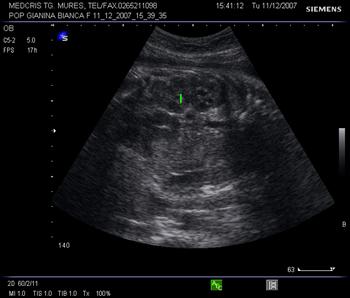

ficat: anecogen, cu structura moderat ecogenica. Locul unde vena ombilicala se varsa in sinusul port se poate identifica si reprezinta un punct de reper pentru biometria abdominala.[8]